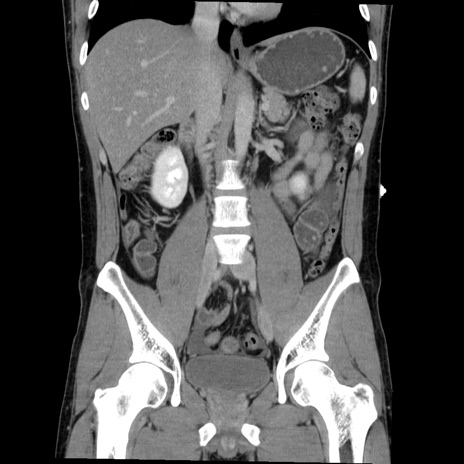

症例36(冠状断像)

【症例】20歳代 男性

【主訴】心窩部痛

【現病歴】今朝より上腹部痛あり。一旦軽快していたが再度出現したため救急要請。昨日夕に白身の魚を含む刺身を食べた。

【身体所見】BP 136/89mmHg、HR 74/min、BT 37.0℃、腹部:膨満、軟、心窩部に圧痛あり。反跳痛なし、筋性防御なし、腸雑音やや亢進あり。

【データ】WBC 17700、CRP 0.48